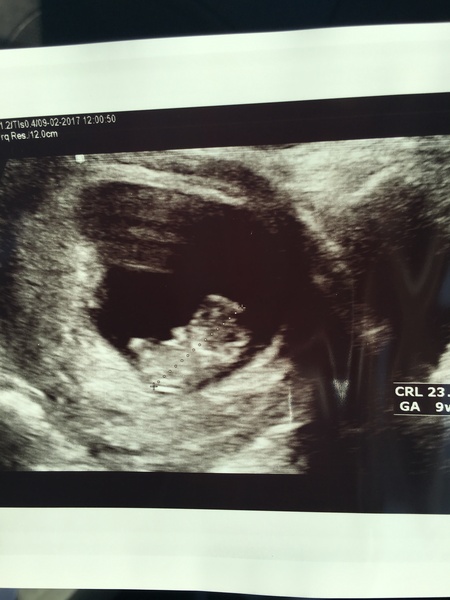

I had a scan today at the EPU because of my pink discharge I'd been having...baby was perfect and wriggling tiny arms and legs on the screen almost like he was waving at me! I was soooooo relieved!